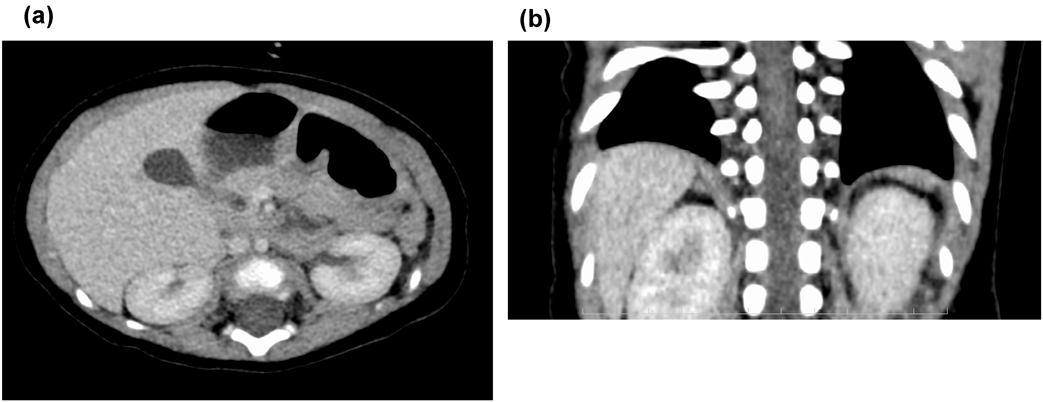

Fig. 4 Abdominal contrast CT

(a) axial plane; (b) coronal plane: Spleen cannot be identified.

入院後,気道感染に伴う気管支喘息の増悪としてステロイドの全身投与,吸入による治療を開始した.しかし喘息としてはステロイド,β刺激薬に対する治療への反応に乏しく入院2日目に中止した.入院3日目に喘鳴の増悪を認め,High-flow nasal cannula(HFNC)を導入した.吸気性喘鳴の鑑別のため耳鼻科でファイバー検査を施行したが喉頭軟化症を含め上気道狭窄病変は認めなかった.入院5日目に再度発熱したため採血を再検したところWBC 24200/µL,CRP 1.4 mg/dLと炎症反応の上昇を認め,ABPC/SBT(134 mg/kg/day)の投与を開始した.鼻腔から喉頭までの気道狭窄病変を認めないにもかかわらず,喘鳴が持続したため下気道評価の目的に造影CTを行うこととした.また,事前に鎖肛治療のために受診していた病院の画像・情報提供を取り寄せたところ無脾症候群の疑いがあることが判明したため,腹部も撮影する方針とした.入院9日目に行った造影CTでは心臓・大血管については右大動脈弓であり,左鎖骨下動脈起始異常を伴っていた.水平断では左鎖骨下動脈は気管の後ろを走行していたが気管の圧排・変形は認めなかった.血管走行の異常は認めたが,気管を圧排する所見がなかったことから,血管輪,vascular slingによる喘鳴は否定的と判断した.肺静脈還流異常も含め複雑心疾患は認めず,心耳形態は正常であった(Fig. 3a–e).肺については,右肺は三葉,左肺は二葉で肺葉に相同性はなかった.気管については,右上葉気管支が気管分岐部よりも上部から分岐しており気管気管支の形態であった.気管気管支に加えて右中葉・下葉に向かう気管支が正中をまたいで左から右に遊走する気管走行をしておりbridging bronchusであった.右上葉気管気管支が分枝するレベルで狭窄を認めており喘鳴の原因と考えられた.腹部所見では胆嚢は描出されたが,脾臓は同定できなかった(Fig. 4a, b).後日再検した血液像でHowell Jolly小体を1%認め,複雑心疾患を伴わない無脾症候群と診断した.喘鳴は徐々に改善し,入院9日目にはHFNCから離脱し,入院11日目に退院となった.以降,かかりつけ病院で抗菌薬の予防内服が開始された.